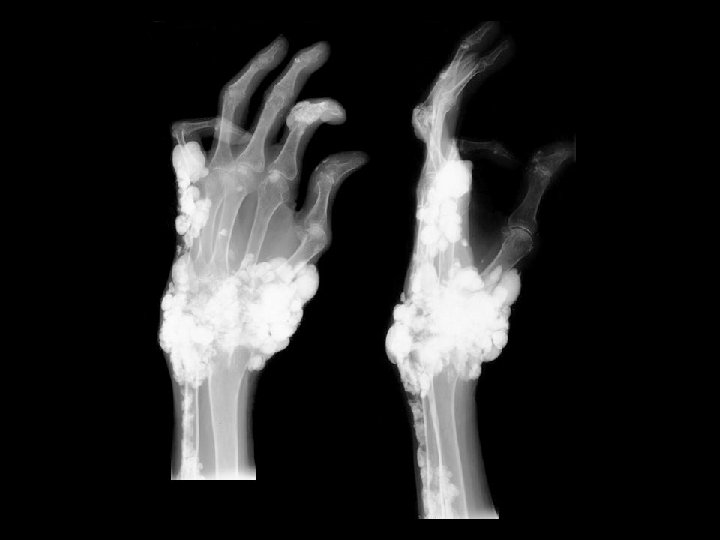

Tumoral Calcinosis • Findings: – Multiple dense calcifications around the joints of the fingers and wrists • ddx: (soft tissue Ca 2+) – Renal osteodystrophy – Heterotopic ossification – Metastatic Ca 2+ – Milk-alkali syndrome – Hypervitaminosis D – Scleroderma – Dermatomyositis